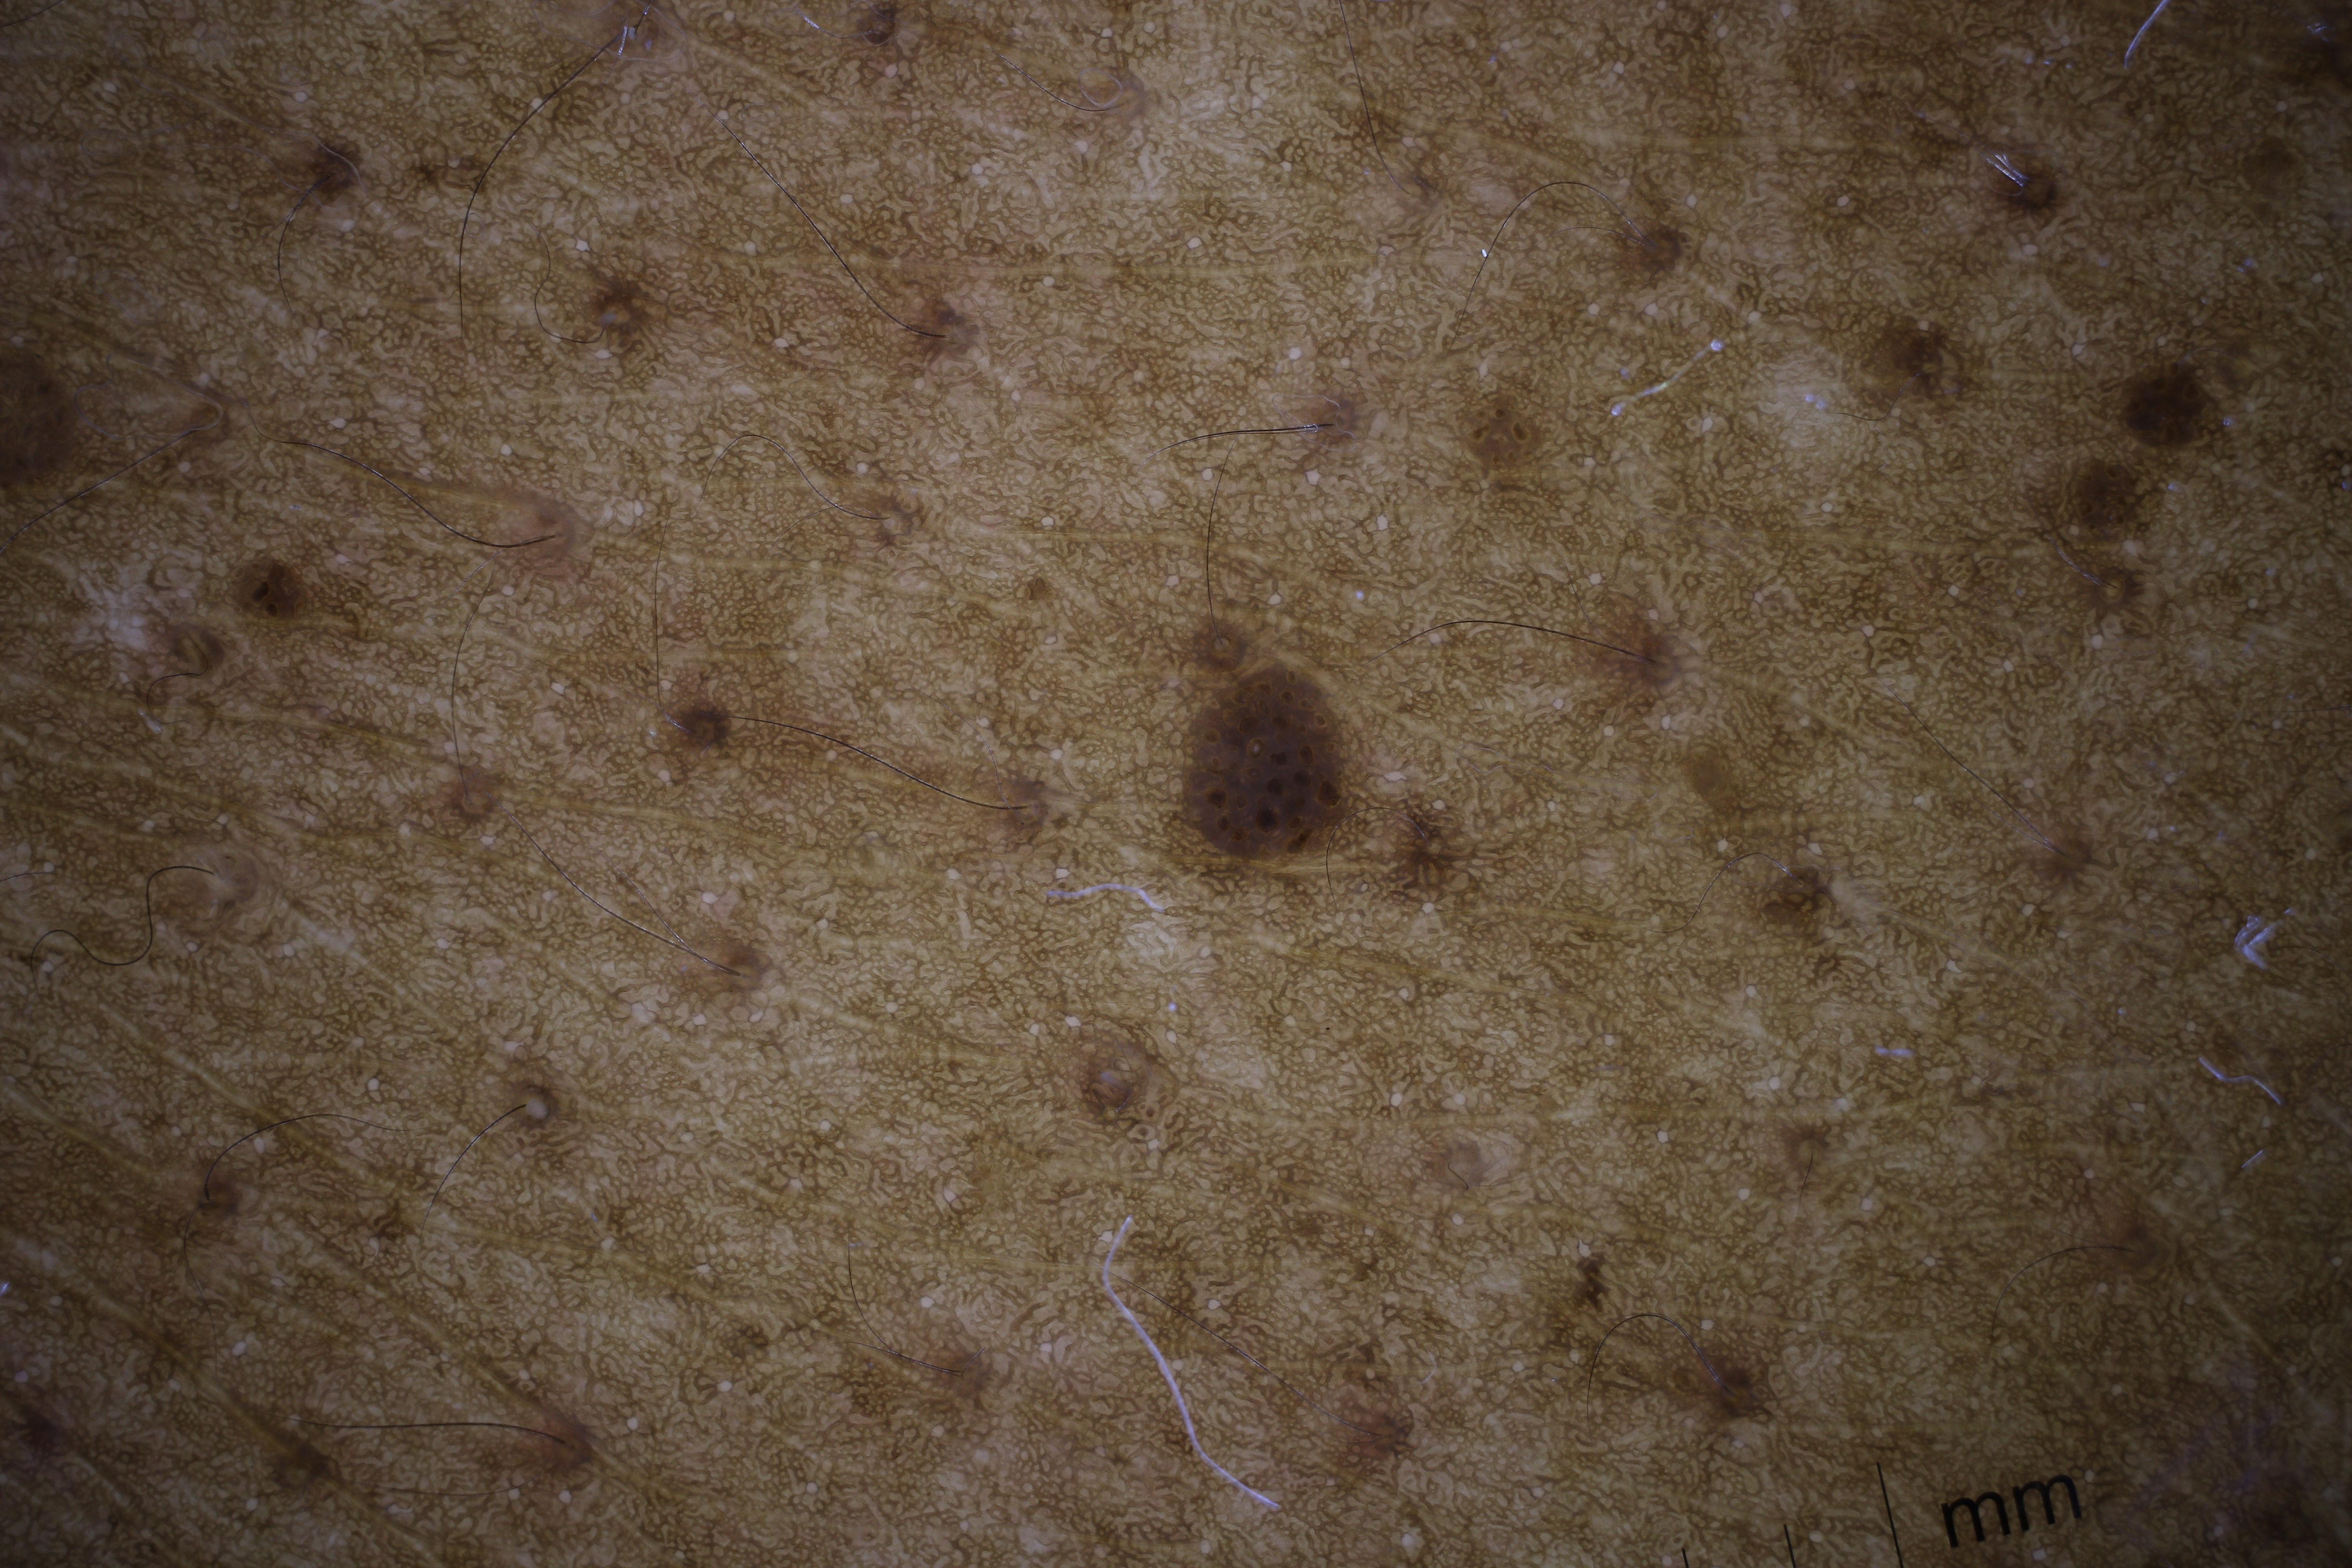

ISIC_6598546

Public

Information

- Created

- Dimensions

- 6000 x 4000

- Attribute to

- Memorial Sloan Kettering Cancer Center

- License

- CC-BY

- Used in

- -

- Belongs to

- IP_8590441 IL_6711989

Clinical

| Field | Value |

|---|---|

| age_approx | 60 |

| anatom_site_1 | Trunk |

| anatom_site_2 | Posterior trunk |

| concomitant_biopsy | False |

| dermoscopic_type | contact polarized |

| diagnosis_1 | Benign |

| diagnosis_confirm_type | single contributor clinical assessment |

| fitzpatrick_skin_type | VI |

| image_manipulation | instrument only |

| image_type | dermoscopic |

| lesion_id | IL_6711989 |

| patient_id | IP_8590441 |

| sex | male |